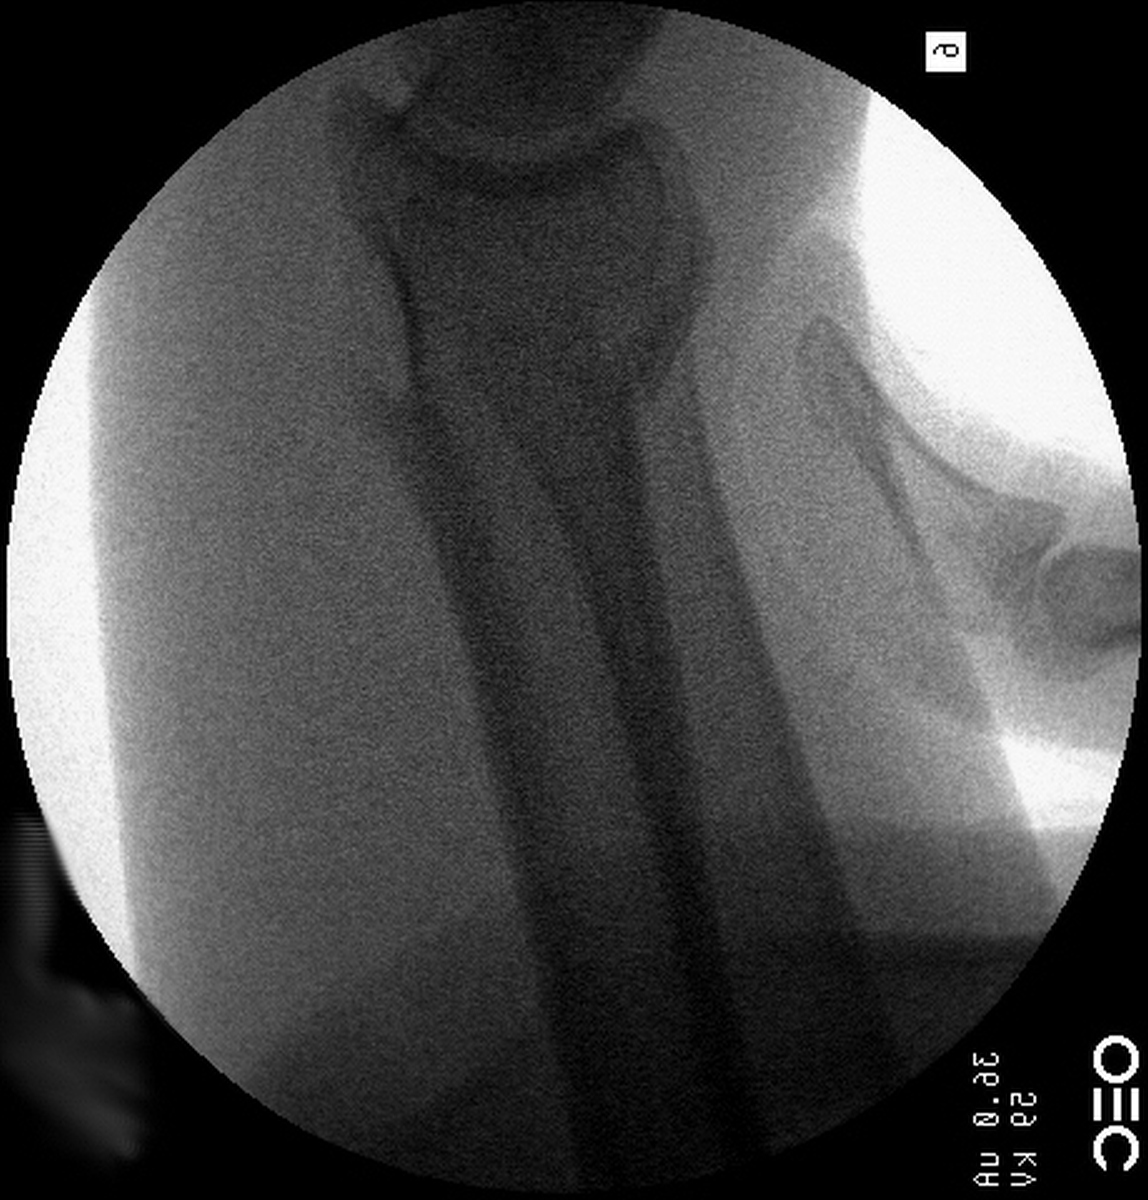

| Freer elevator

introduced percutaneously as a reduction aid. |

| Percutaneous

fracture stabilization with three pins via the

dorsal radial tubercle, radial styloid and FCR

portals. |